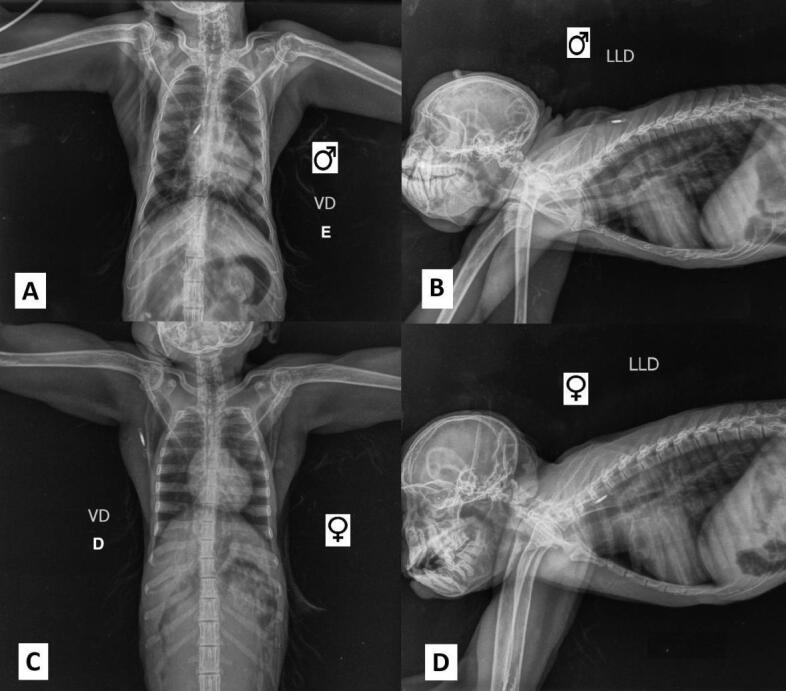

类蚓蛔虫感染是一项重大的全球卫生挑战,影响人类和非人类灵长类动物。在非人灵长类动物中,类蚓蚓感染对保护工作构成重大威胁,因为它们可以影响圈养种群和野生种群,引起从轻微到严重的并发症。本研究报告了在动物园饲养的两只黑sakis (Chiroptes uttahickae),一只雄性和一只雌性,由于体重减轻而进行常规检查。超声检查显示肠内有大量大蛔虫。雌鼠给予吡喃吡酯治疗,雄鼠给予芬苯达唑治疗,均取得成功。这些蠕虫被送去进行形态学和分子鉴定,并提交给新的检查。这一病例强调了在动物园进行预防性兽医检查的重要性,特别是对构成人畜共患病风险的寄生虫进行检查,以确保动物和人类健康。

Ascaris lumbricoides infections represent a major global health challenge, affecting both humans and non-human primates. In non-human primates, A. lumbricoides infections pose a significant threat to conservation efforts, as they can impact both captive and wild populations, causing complications ranging from mild to severe. This study reports the case of two black sakis (Chiroptes utahickae) kept under human care in a zoo-a male and a female-presented for routine examination due to weight loss. Ultrasonography revealed a substantial intestinal infestation of large roundworms. The female was treated with pyrantel pamoate, and the male with fenbendazole, both with successful outcomes. The worms were sent for morphological and molecular identification, and the animals were submitted for new examinations. This case underscores the importance of preventive veterinary check-ups in zoos, particularly for parasites that pose zoonotic risks, to ensure both animal and human health.